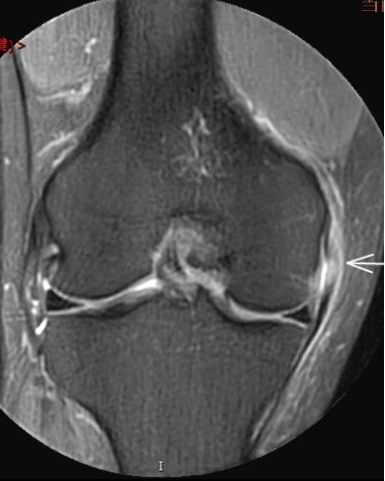

2. 運(yùn)動(dòng)后“打軟腿”——韌帶的“斷弦危機(jī)”

場景:打球急停后膝蓋不穩(wěn),走路像“踩棉花”

MRI偵查:揪出前交叉韌帶斷裂(呈“波浪狀”或連續(xù)性中斷)、內(nèi)側(cè)副韌帶損傷,防止關(guān)節(jié)“脫軌”

(內(nèi)側(cè)副韌帶損傷)